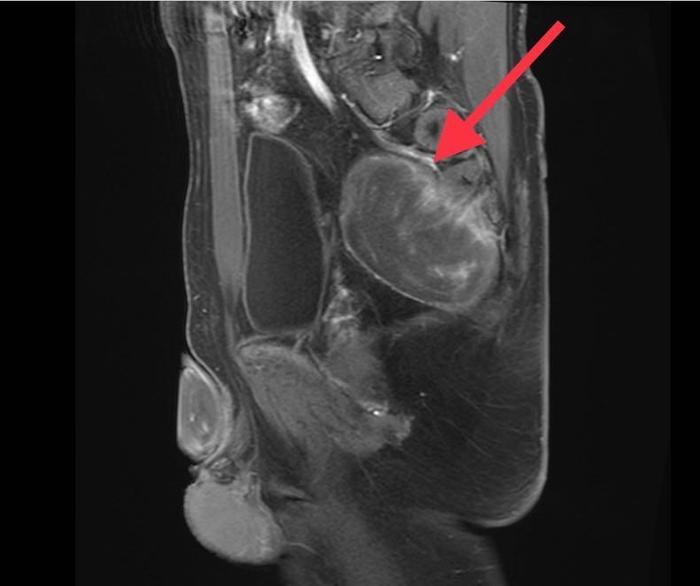

近日,余先生行色匆匆地来到同济大学附属东方医院胃肠肛肠外科傅传刚教授特需就诊,他自述自己既没有排便习惯的改变,身体也没有其它不舒服,但就是10天前在外院做B超检查时发现盆腔低回声,此外MR检查提示骶前直肠后可见一等T1,混T2回声,大小50*72*91mm肿物,结肠镜提示可见腔外压迫。余先生为此感到焦虑,难道自己得的是癌症?还是什么其他的疾病?他思虑万千,恳求傅传刚教授一定要帮他查出自己到底患了什么疾病!

傅传刚教授给余先生安排进行了详细查体和辅助检测。查体发现肛门外形正常,直肠指诊后壁齿线上约3cm向上可触及巨大肿物下缘,粘膜完整。盆腔(MRI增强)显示盆底占位,考虑神经源性肿瘤可能。

傅传刚教授结合余先生的病史、症状、体征、MR等,诊断明确,傅传刚教授和周主青教授于2020.09.14共同实施腹腔镜骶前肿瘤切除术